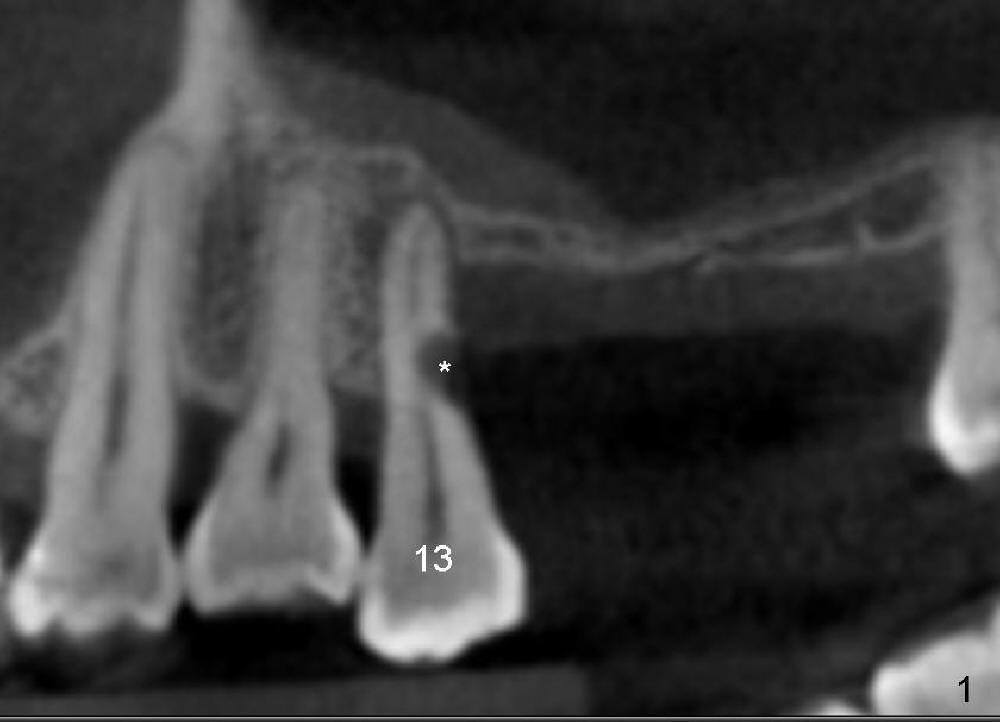

A 44-year-old man has severe periodontitis. The tooth #13 has a distal cervical carious lesion with spontaneous pain (Fig.1 (CT sagittal section) *). The caries is continuous with the buccal canal (Fig.2 (coronal), 3 (axial section) *).